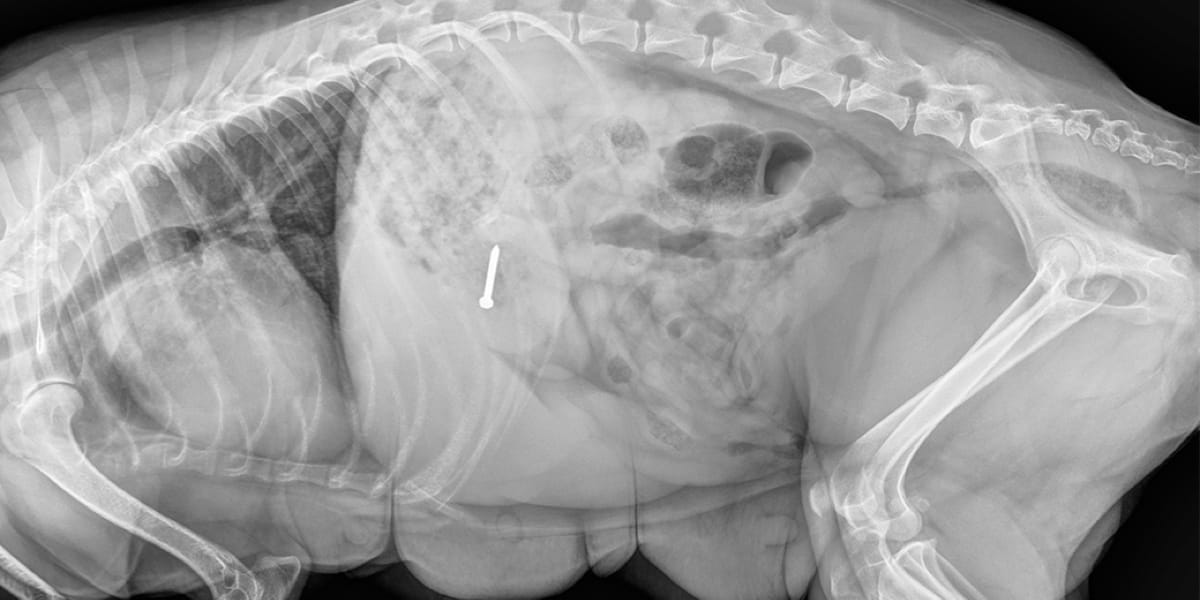

Kedi ve Köpeklerde Yabancı Cisim Yutması

Kedi ve köpekler son derece meraklı canlılardır. Özellikle yavru hayvanlarda, her şeyi ağızlarına götürme eğilimi daha yüksektir. Bu yüzden yabancı cisim yutma vakaları, Ankara’daki veteriner kliniklerine en sık gelen acil durumlar arasında yer alır. Kedi veya köpeklerde yabancı cisim yutması, basit bir sorun gibi görünse de bağırsak tıkanması, iç kanama ve hatta yaşamı tehdit eden […]